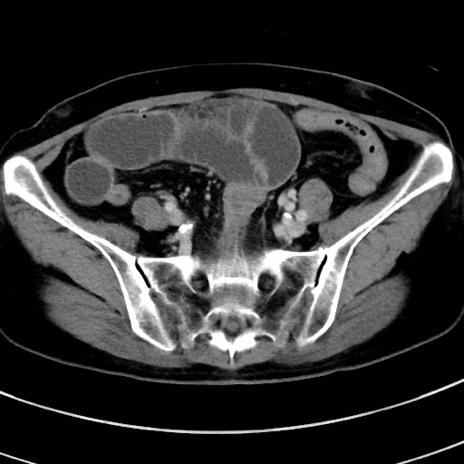

症例9(横断像)

【症例】 60歳代女性

【主訴】むかつき、みぞおちの痛み

【現病歴】3日前よりむかつきがあり、食事がとれない。

【既往歴】糖尿病

【身体所見】発熱なし、心窩部圧痛軽度あるも、腹膜刺激症状なし。

【データ】WBC 7400、CRP 1.92